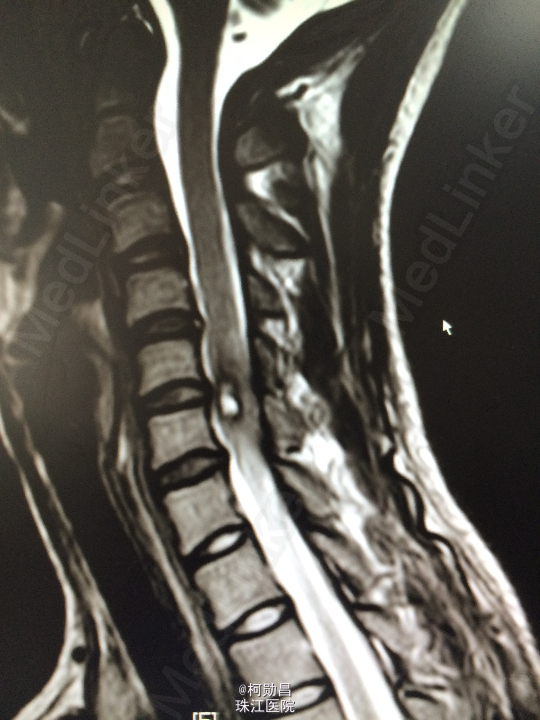

主诉:颈部疼痛伴右手麻木疼痛2月余 病史:患者缘于去年11月份无明显诱因出现右侧上肢乏力,右手小指及无名指疼痛麻木感,无头痛头晕,无间歇性跛行等,在当地医院行MR提示:颈椎椎管内占位性病变,予对症治疗后效果不佳。期间上述症状加重,遂至我院进一步诊治。

查体:颈椎下端棘突间轻压痛,颈椎活动受限,双臂丛牵拉试验阳性,压头试验阳性。四肢肌力5级,感觉:右侧前臂尺侧小指及无名指痛、触觉稍减退,余肢体及鞍区疼痛觉正常。反射:右侧肱二头肌腱反射亢进,左侧肱二头肌腱反射稍亢进,左侧肱三头肌腱反射活跃,双侧挠骨膜腱反射康静,双侧膝腱反射正常。余反射正常。病理征:右侧Hoffman征弱阳性,左侧Hoffman征正常,余征均正常。 辅助检查:颈4-6椎体水平髓内出血信号,海绵状血管瘤伴出血?

诊断:C5/6脊髓内海绵状血管瘤并出血。 处理:予手术切除治疗